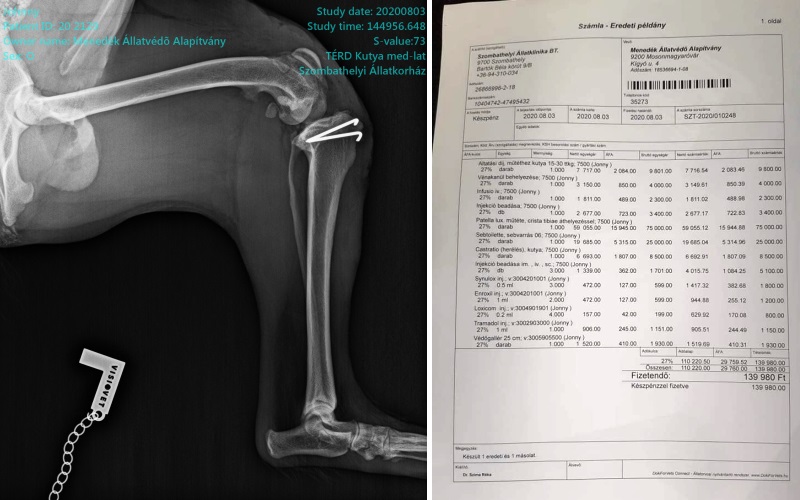

Még hosszú az út a gyógyulásig, de mi bízunk benne, hogy sikeres volt a műtét. Egyelőre kennel nyugalom, aztán fizioterápia vár rá. Sajnos senki nem jelentkezett hogy befogadná ideiglenesen, ezért megint nekünk kellett varázsolni. Így egyik tagunk vitte haza, és saját otthonában gondozza. Köszönjük azoknak, akik anyagilag támogatták Johnny gyógyulását! Továbbra is várjuk/várnánk ideiglenes befogadók jelentkezését, mert sajnos ezt így már nem bírjuk! (2020-08-06 08:47:54)